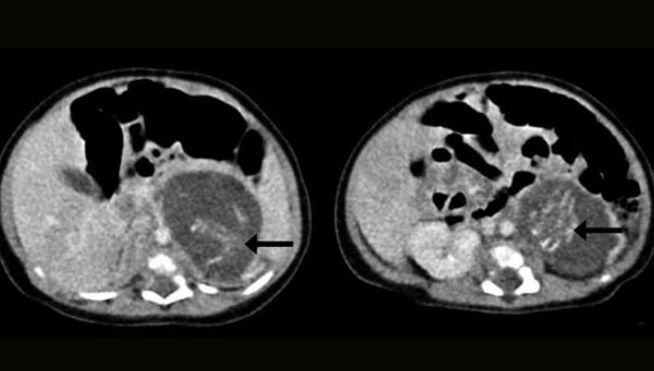

Una neonata incinta di due gemelli? Sì, è possibile. La piccola è venuta al mondo in Cina con una rara situazione: era incinta di due gemelli. I medici, all’inizio, pensavano di trovarsi davanti ad una ‘semplice’ malformazione, invece la piccola aveva dentro di se ben due feti. Tale patologia prende il nome di fetus in fetu. La bambina è stata in seguito sottoposta a intervento chirurgico per asportare i due feti.

Alla terza settimana di vita della neonata, i medici hanno asportato i feti dal suo corpicino quando erano rispettivamente di 8 e 10 settimane. I due feti erano dotati entrambi di cordone ombelicale, spina dorsale e piccoli organi in formazione.